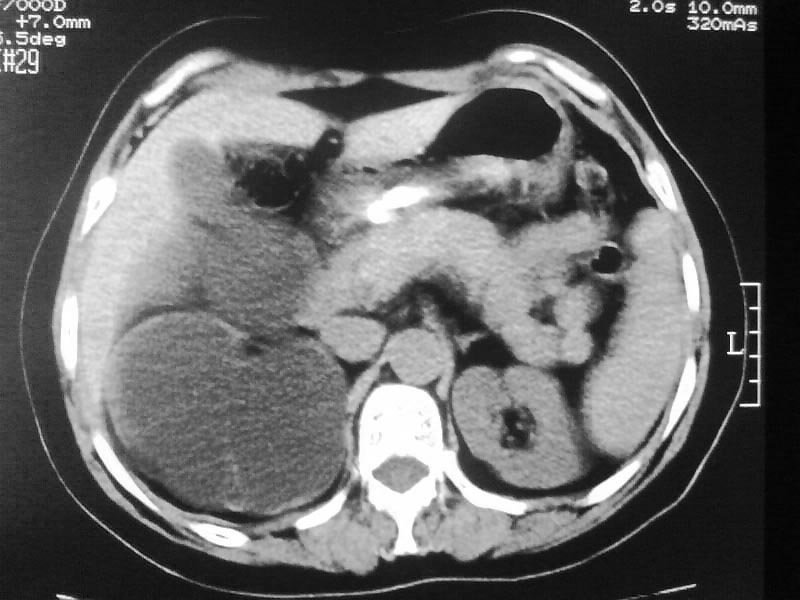

标题: CT20044:女,45岁,腰痛2年,双肾结石,右输尿管结石,右肾重度积 [打印本页]

标题: CT20044:女,45岁,腰痛2年,双肾结石,右输尿管结石,右肾重度积

支持双肾结石、右输尿管上端结石,右肾重度积水

右肾梗阻性积水。

支持 右肾结石、右输尿管上端结石,右肾重度积水。